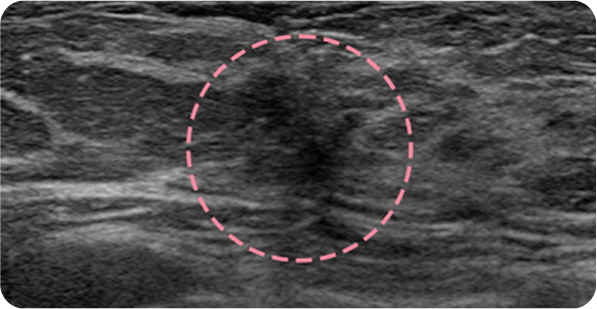

외국에서 내원한 17세 환자분은 빠르게 자라는 큰 유방 종양으로 대학병원 수술이 권고되었으나, 고난도 시술 경험을 바탕으로 3차례 맘모톰을 통해 성공적으로 제거했습니다. 흉터를 걱정했던 환자와 보호자 모두 결과에 만족하며, 현재까지 정기 추적검사에서 깨끗한 상태를 유지하고 있습니다.